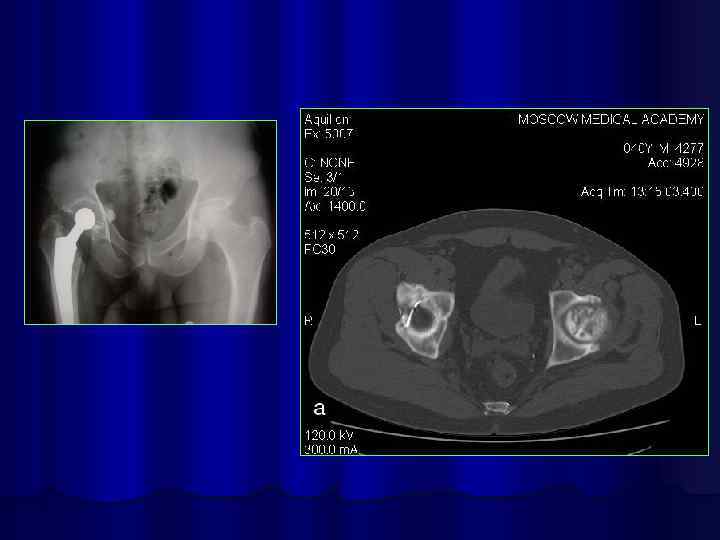

Искусственный сустав

Коксартроз